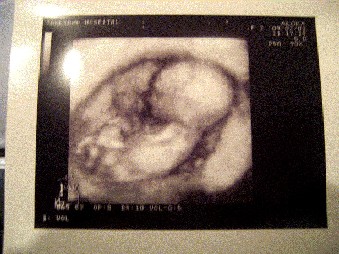

で最近のベビちゃんの状況はこんな感じ。

最近形がはっきりしてきたなぁ。